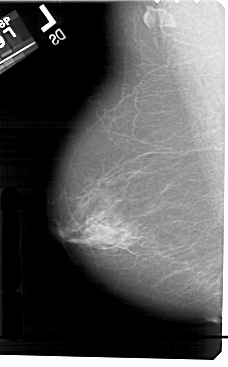

A_1574_1.RIGHT_MLO

RIGHT_MLO LINES 5491 PIXELS_PER_LINE 3346 BITS_PER_PIXEL 12 RESOLUTION 43.5 OVERLAY